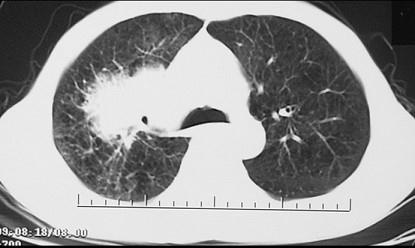

问题 男,68岁,右侧胸痛伴右上臂麻木1周,胸部CT、MRI扫描如图,最可能的诊断为 ( )

选项 A.右上肺硬化性血管瘤 B.右上肺肉瘤并纵隔淋巴转移 C.右上肺不张 D.右上肺中央型肺癌并右上肺不张,纵隔淋巴转移 E.右上肺周围型肺癌并纵隔淋巴转移

答案 D